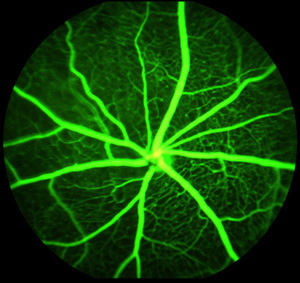

研究人員也查看了小鼠的眼睛。像任何其他器官一樣,在眼睛中有新血管生長以應對疾病或損傷。但是不同于身體其他部位,此處的新血管并不理想,因為它們出血,造成瘢痕組織形成并阻止光傳到視網膜,引起視力喪失。

相反,抑制眼睛中的這些通路,可能有助于老年性黃斑變性或糖尿病性視網膜病患者。這些患者生出新的血管來應對這些病變或受損狀態,但是新的血管只用來遮擋視線,并不能幫助治愈異常的眼疾。

Barnes-Jewish 醫院的Apte稱:“這是重要的一點。在糖尿病中,因為疾病的影響,視網膜的正常血管變得脆弱。用任何一種靶向治療,我們都擔心會破壞正常的血管。但是我們的研究表明,抑制眼睛中的FGF信號,可以預防這種異常的反應,而不會傷害正常的血管。”